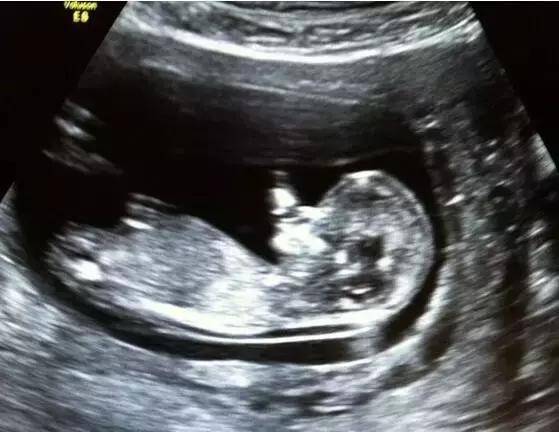

4、早孕期超声检查可以确定宫内妊娠和孕周,确定胚胎数目。孕5周左右的B超可见孕囊,6周左右可见胎芽及原始心管搏动(确定活胎)。有部分孕妇平时月经不规律,或者此次受精晚,未见胎芽胎心,应重新核算孕周,推迟两周复查超声。

11-13+6周之间的B超可以看到“胎儿颈部透明带”,又称NT超声,是早期筛查胎儿畸形的检查。